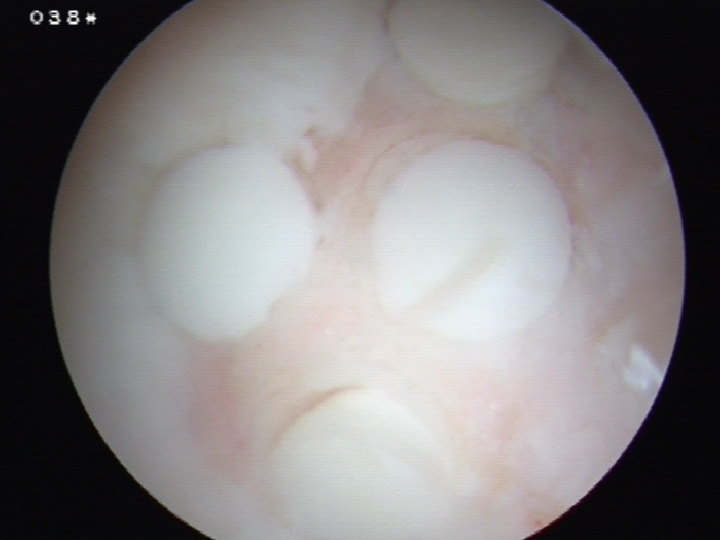

Osteochondral autograft transplantation / mosaicplasty

Principle

Autologous osteochondral bone plugs implanted in defect

- taken from low weight bearing areas of the knee

Technique

Debride all tissue from defect

- obtain osteochondral plugs 4.5 mm

- periphery of femoral trochlea / notch

- create cylindrical holes with drill

- insert osteochondral plug

- small gaps between plugs

- ensure slightly recessed